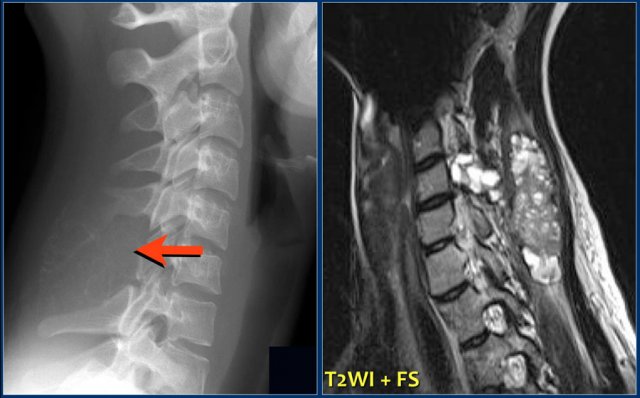

Here images of a patient with lytic lesions of the C2 and C3 vertebrae with cortical destruction posteriorly.

The differential diagnosis based on the CT-findings includes primarily metastases and myeloma.

The sagittal T2-weighted image with fat saturation demonstrates continuity between the abnormalities with soft tissue extension and compression of the myelum.

Now our differential should also include chordoma which has its origin in the neural axis as it arises from notochord remnants.